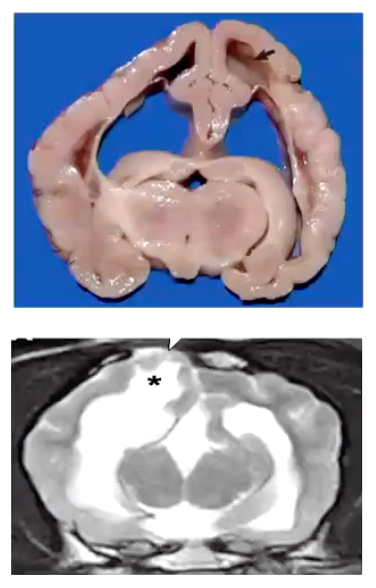

What are the characteristics of hydranencephaly?

• Almost complete loss of one or both cerebral hemispheres which is replaced by CSF (=cerebral cavity)

• It was initially well-formed but is destroyed.

• Almost complete absence of cerebral cortex, reduced to a thin layer.

• The adjacent skull may be abnormal too.

What are some of the main causes of hydranencephaly?

Perinatal stroke = lack of perfusion of cells = necrosis.

Viral infection = destruction of germinal layer

(Cattle: Bovine Viral Diarrhoea, virus, Blue tongue virus, etc...; Cat: Panleukopenia virus).

Genetic transmission in sheep

What are the signs of hydranencephaly?

• Signs:

• Seizures - most commonly + Mild deficits: unilateral/bilateral blindness.